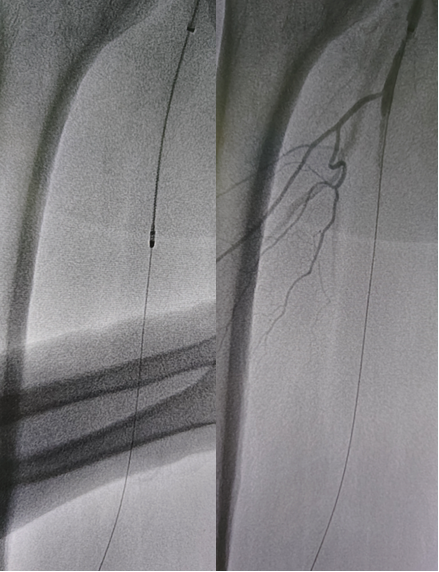

病例1(股腘动脉CTO):

一例重度间歇性跛行患者,导丝通过股腘动脉CTO病变后,若仅凭DSA判断,可能直接进行Rotarex减容。但IVUS检查发现导丝实际位于内膜下(假腔)。此时若进行减容,风险极高。术者遂调整策略,改用球囊扩张后植入Viabahn支架,成功避免了严重并发症。

病例2(股腘动脉长段闭塞):

另一例长段闭塞病变,IVUS证实导丝真腔通过后,指导术者选择了合适尺寸的Rotarex导管进行减容,联合普通球囊(POBA)预扩及DCB治疗,获得了满意的管腔,避免了支架植入。

图:导丝通过后3mm球囊预扩

图:多处假腔通过,遂5mm球囊预扩